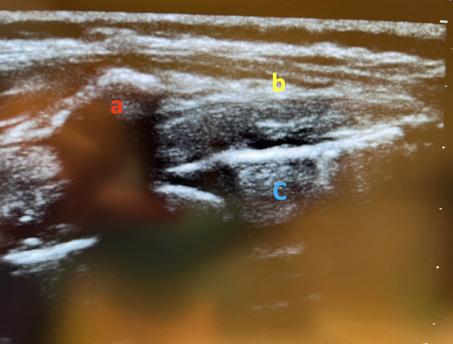

Table des illustrations

1. Korte, Wolfgang: Moderne Gerinnungsdiagnostik: wie hilft sie uns? http://www.anaesthesie-stgallen.ch/ Informationen_fuer_Fachpersonen/Fruehere_Veranstaltungen/IPS_Symposium_2008/05Korte.pdf

2. Görlinger K, Bergmann L & Dirkmann D. Coagulation management in patients undergoing mechanical circulatory support. Best Pract & Res Clin Anaesthesiol. 2012;26:179-198.

3. et 4. Gauger MS, Kaufmann P, Kamber F et al. Rotational Thromboelastometry Values After On-Pump Cardiac Surgery – A Retrospective Cohort Study. Semin Cardiothorac Vasc Anesth. 2022;26:209-220.

Laufbahnplanung auf

Die ideale Plattform für Berufs- und Bildungsprofile von Gesundheitsfachpersonen, weil

•alle Diplome und Zeugnisse an einem Ort zentral und elektronisch abgelegt sind

•ein stets aktueller Lebenslauf generiert werden kann